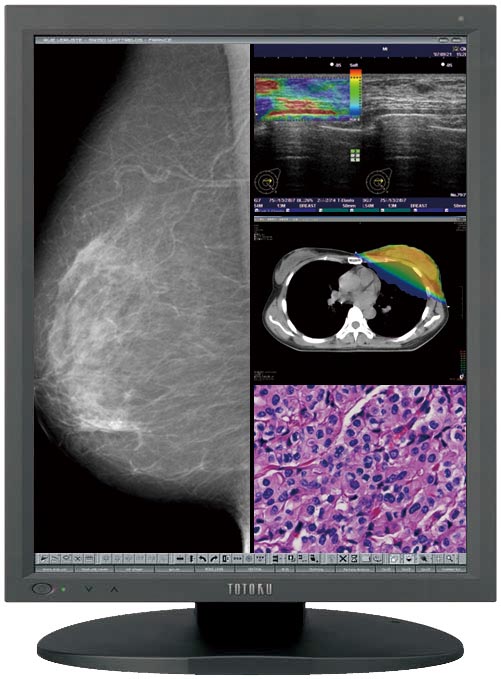

TOTOKU、医用画像表示向けの高精細21.3型液晶ディスプレイ,

TOTOKU、医用画像表示向けの高精細21.3型液晶ディスプレイ, 2025 国際医用画像総合展(ITEM 2025)」に出展 | 株式会社JVC,

2025 国際医用画像総合展(ITEM 2025)」に出展 | 株式会社JVC, ソフトウェア | 製品情報 | TOTOKUディスプレイ,